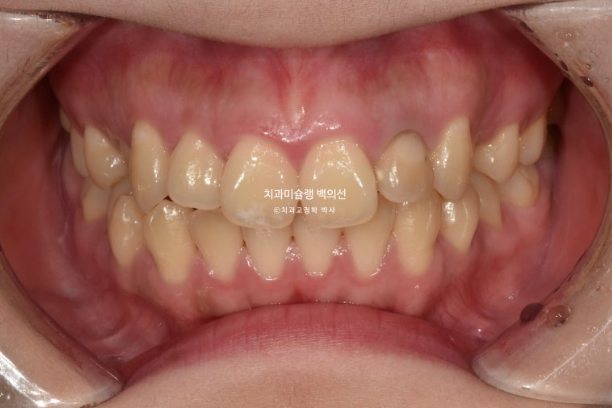

23년 12월 교정치료를 위해 멀리 지방에서 오신 환자분입니다.

환자가 고치고 싶은 것은 배열, 교합, 거미스마일(잇몸미소) 마지막은 비대칭 입니다.

엑스레이 검사 결과 뼈의 비대칭은 경미하나 상하 치아중심선이 어긋나있어서 이 부분 개선을 원하셨습니다.

교합은 거꾸로 물리는 어금니 반대교합도 있고, 뜨는 부분도 있고 앞니 하나는 신경치료 후 변색이 되어 있습니다.

작은어금니가 입천장으로 들어가 있어 반대교합 상태였습니다.